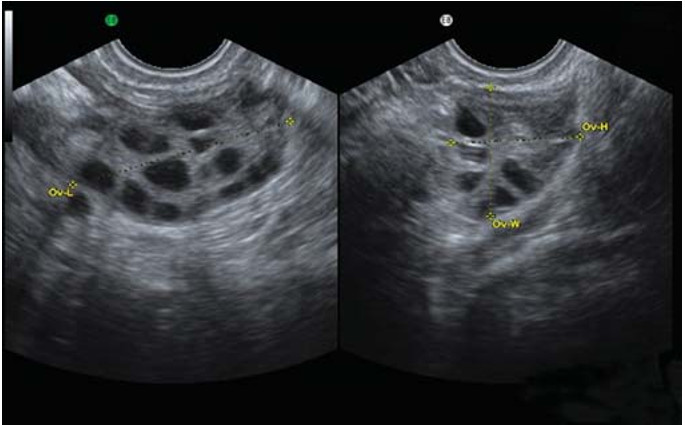

在做超声检查时发现两边卵巢长出许多小囊(内含有卵子),这些小囊大小约2~8mm,小囊数目每边卵巢约10个以上,会造成卵巢发育不正常且无法定期排卵。

4、卵巢结构异常

影像学检查发现卵巢有变大的情形,或是在卵巢发现超过12颗以上的滤泡。